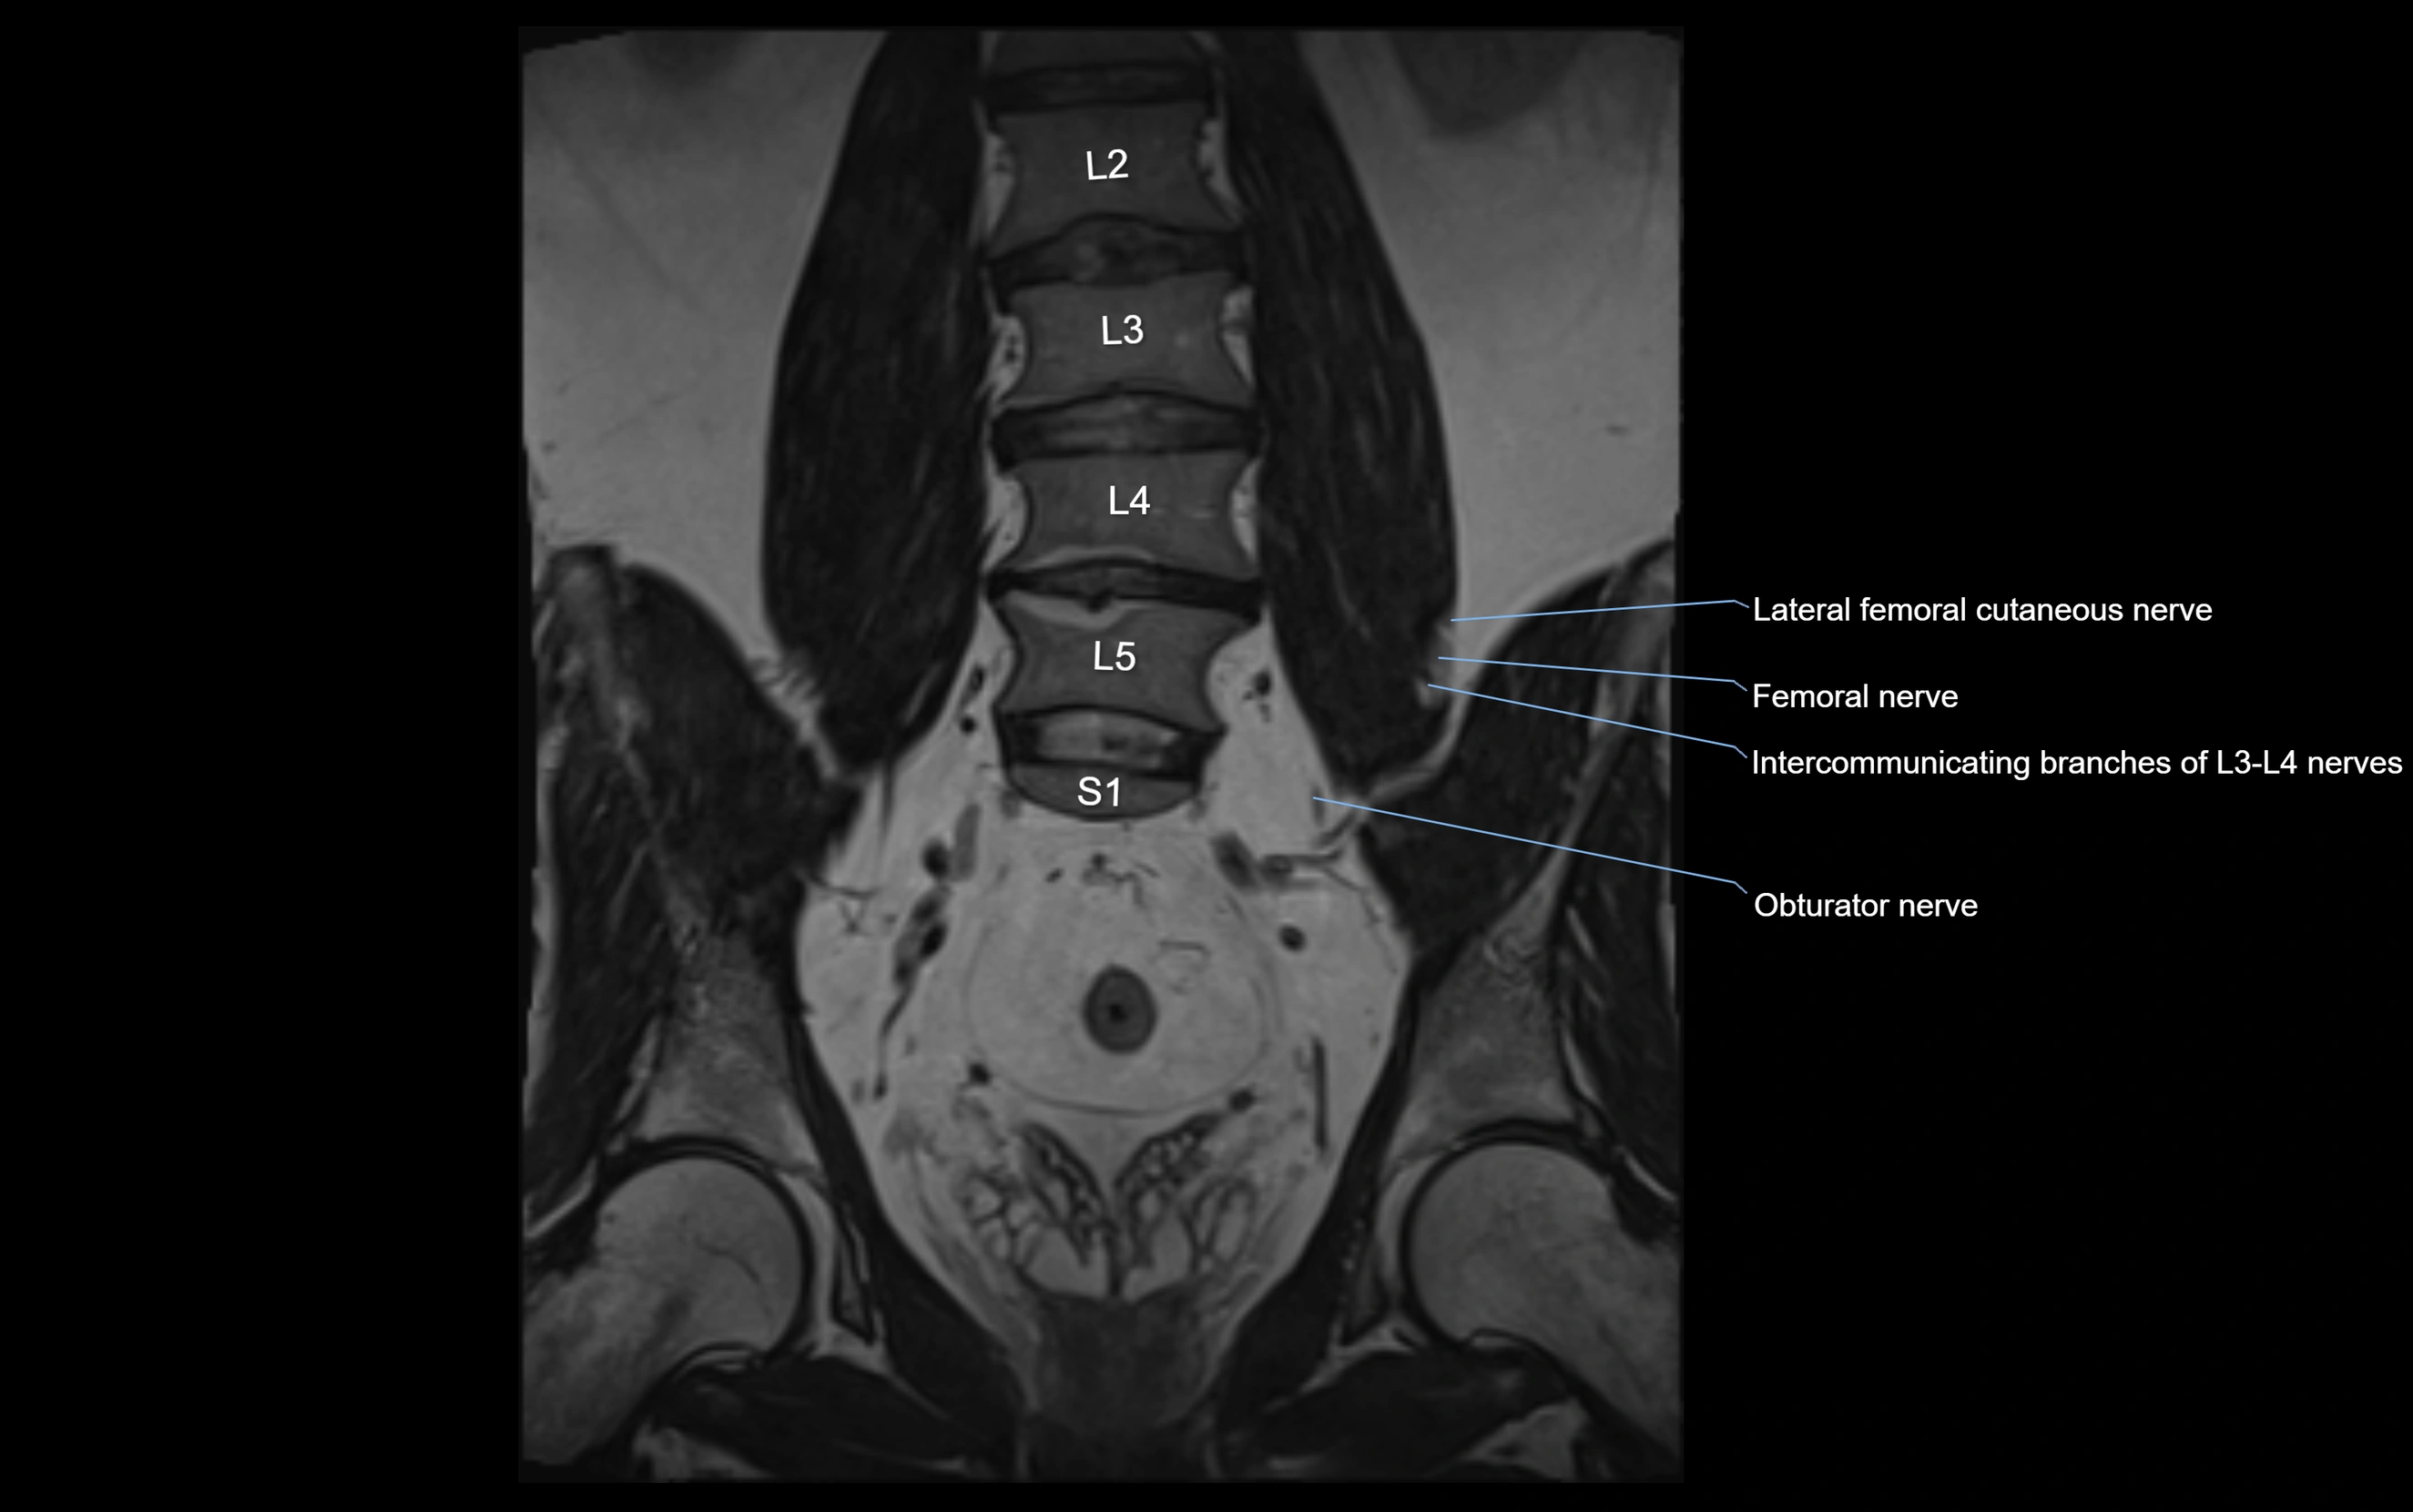

MRI Appearance

T1-weighted images:

• Nerve appears as a very thin low-to-intermediate signal intensity structure

• Surrounded by bright fat, aiding visualization

T2-weighted images:

• Nerve shows intermediate to mildly hyperintense signal compared to muscle

• Pathological involvement appears brighter

STIR (Short Tau Inversion Recovery):

• Normal nerve appears dark

• Inflamed or entrapped nerve appears bright hyperintense

T1 Fat-Sat Post-Contrast:

• Normal nerve enhances minimally

• Pathologic nerve (neuritis, entrapment, tumor infiltration) shows focal or diffuse enhancement

3D T2 SPACE / CISS:

• Nerve appears intermediate to mildly hyperintense compared to muscle

• Surrounded by bright fat or CSF, improving visualization

• Best sequence for mapping small pelvic nerves such as the anococcygeal